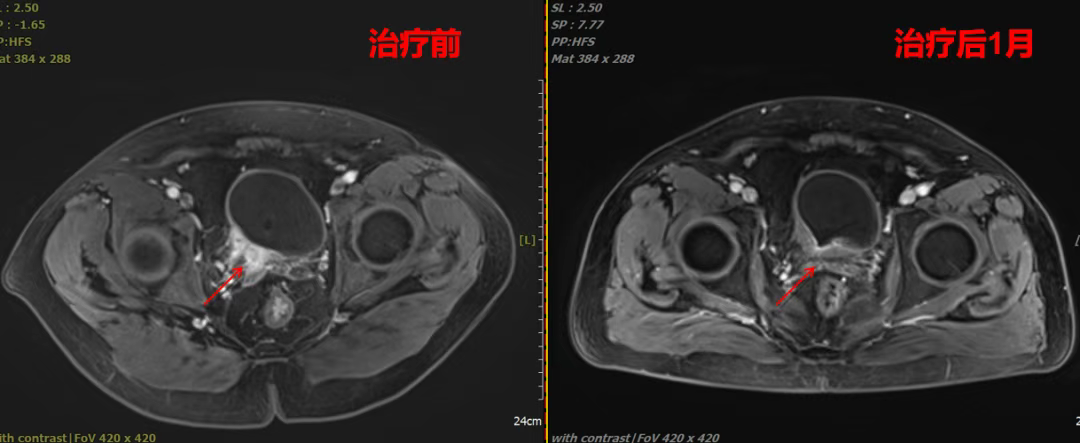

✅ 疗效显著,1个月肿瘤退缩

●治疗后1月评估为PR(部分缓解),肿瘤代谢活性大幅降低,右侧输尿管压迫明显改善。

●影像对比